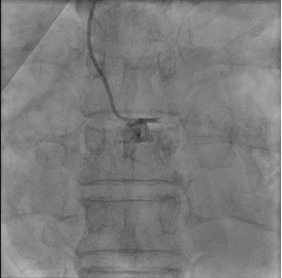

Relevant Test Results Prior to Catheterization

The admission ECG demonstrated ST-elevation in aVR with diffuse ST-depression across the precordial and inferior leads, suspicious for left main coronary occlusion. Bedside echocardiogram showed severe diffuse apical and anterior hypokinesia and a severely impaired left ventricular ejection fraction (LVEF) estimated at 20%.

As patient is having cardiogenic shock from a LM occlusion and refusal of CABG, a high-risk, mechanically-supported PCI was undertaken. An IABP was inserted via the left femoral artery for hemodynamic support.Right femoral artery approach. 7Fr EBU 3.5 Guide. LAD and LCx were wired with microcatheter support. 2.0 balloon was used to predilate the LM-LAD lesion, TIMI 3 flow restored.IVUS was performed, showing heavily calcified plaque throughout the LM and LAD. Based on IVUS sizing (LM: 4.5mm, pLAD: 4.0mm), predilation with NC balloons followed by Intravascular Lithotripsy (IVL) with a 3.0 Shockwave balloon for 70 cycles were performed.A 2.75/40mm DES was placed in the mid-LAD and a 3.5/24mm DES was deployed from the ostial LM into the proximal LAD. POT in the LM using a 4.5 NC balloon, followed by post-dilation of the proximal LAD with a 4.0 NC balloon.Post-angiography revealed a jailed D1 with TIMI 0 flow. Rewiring to D1 was reattempted successfully with a CTO wire. Switched back to workhorse wire, dotted and predilated with 1.5 semi-compliant balloon. However IVUS showed wire likely true-false-true with ostial D1 in subintimal. Decided not to further intervene on D1.Final IVUS showed satisfactory results. Angiogram after adenosine showed regained flow in D1, TIMI 3 flow in both LAD and D1. Patient remained hemodynamically stable on IABP support post-procedure.